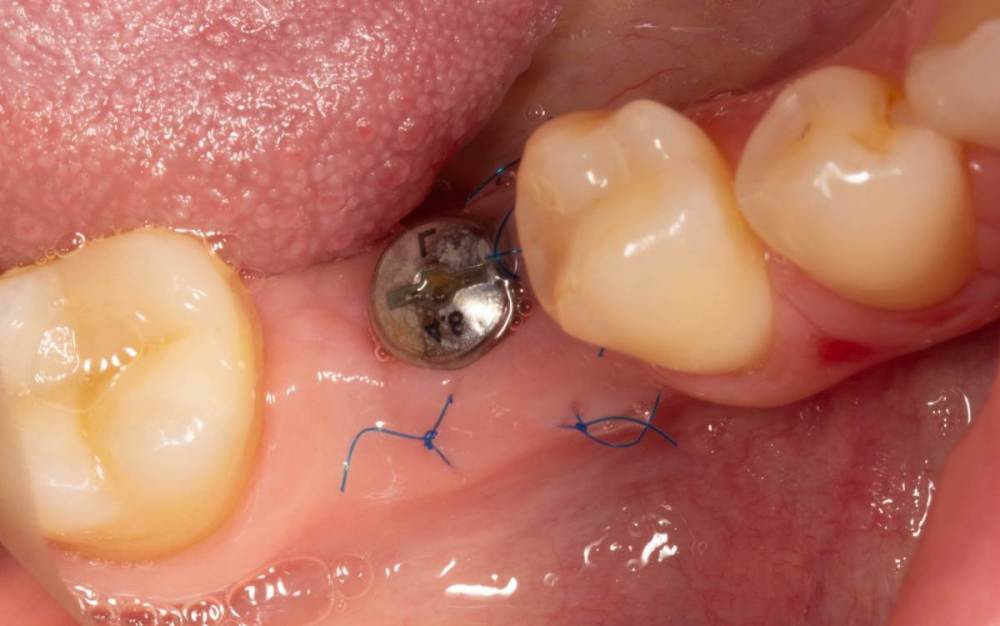

Женька Опубликовано 3 июля, 2023 Автор Поделиться Опубликовано 3 июля, 2023 Возвращаясь к теме) Не фартануло... думаю "ручку" чемодана надо было делать полноценно с захватом сосочков. И перемещать целиком. Через 7 дней ни трансплантата, ни швов, ни объёма( Админ, не получается изображение развернуть и нормально вставить, как я не крутил. Ссылка на комментарий